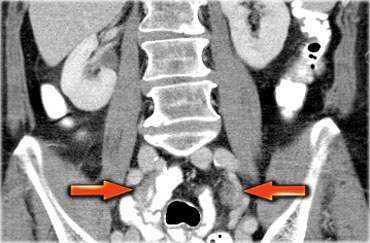

Một phương pháp hữu ích để xác định buồng trứng là theo dõi tĩnh mạch buồng trứng theo hướng đuôi.

Hãy cuộn qua các hình ảnh CT và theo dõi tĩnh mạch buồng trứng phải từ vị trí đổ vào tĩnh mạch chủ dưới, và tĩnh mạch buồng trứng trái từ vị trí đổ vào tĩnh mạch thận trái, cho đến khi xác định được buồng trứng.